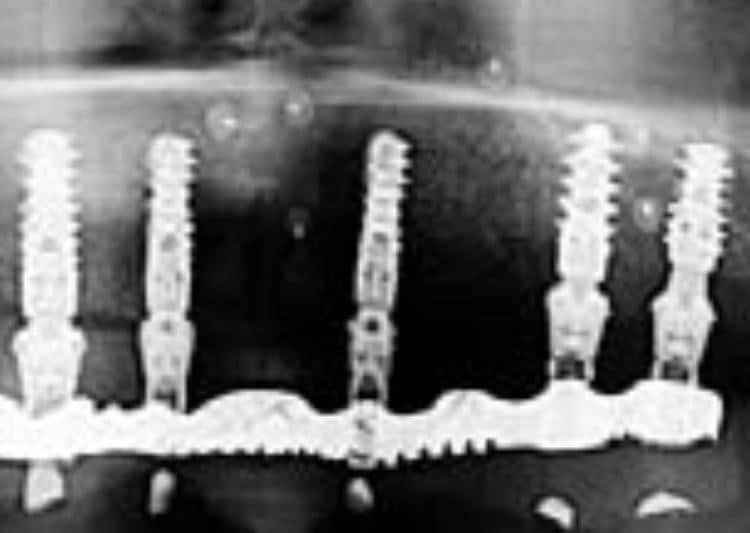

כישלון בשתל דנטלי מיוחס בדרך כלל למצב בו השתל מאבד עיגון בעצם ומפתח ניידות,במילים קצת אחרות השתל מתחיל להתנדנד או חליליה . קודמים לתחנה סופית זו בחיי השתל הם תהליכי הרס של העצם המאחזת של השתל. תהליכים אלה יכולים להתפתח במשך שנים עד לאובדן סופי של היציבות.

כמעט כל יצרני השתלים בעולם מדווחים על אחוזי הצלחה גבוהים במיוחד של כ 95 אחוזים ולמעשה אין הבדלים בין החברות השונות בהתייחס למדד זה. יחד עם זאת באם מגדירים הצלחה או כישלון של שתלים על פי אחוז המקרים בהם חלה ספיגת עצם הרי שאחוזי ההצלחה נופלים בעשרות אחוזים.